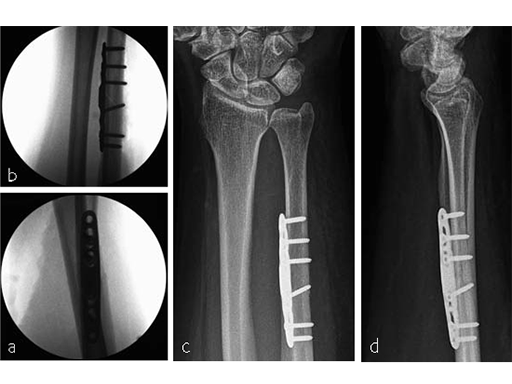

Case 3: Oblique osteotomy

A 48-year-old female nurse had a diagnosis of a degenerative central TFCCrupture, with chronic ulnocarpal abutment.

The amount of correction required was 2.5 mm. The preoperative x-ray showed positive ulna variance.